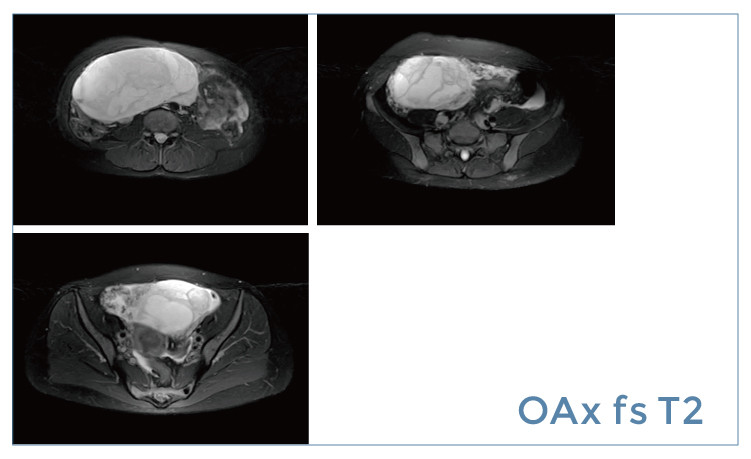

【朗润影像档案】磁共振影像病例分享(编号20190419)

【朗润影像档案】20190419磁共振影像病例结果讨论